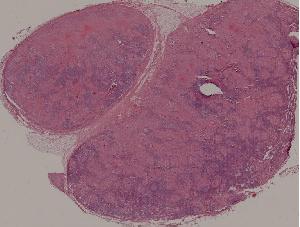

77. Chronic pyelonephritis